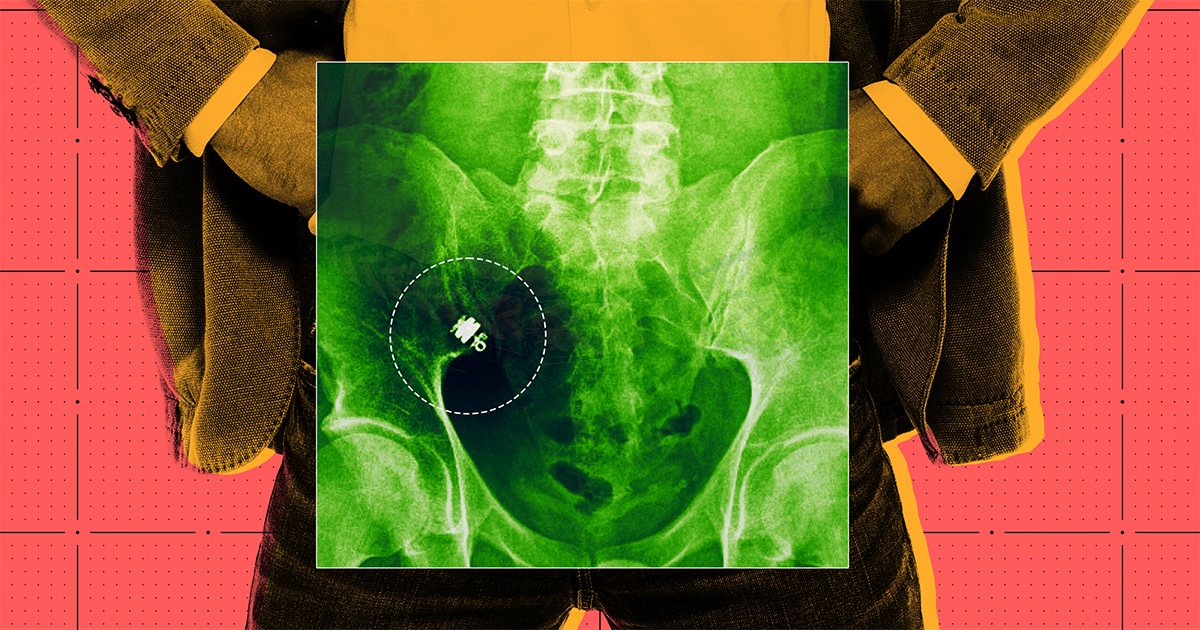

“I went to get this X-ray at 14 days, and I was joking with the X-ray tech, like, ‘if you see some big glowy camera in there, let me know.’ But no part of me thought that it was still in there,” said Thiessen, until they got to the final scan of his lower abdomen.

“Everyone went silent,” said Thiessen. Sure enough, the next day, his doctor confirmed that the camera was stuck.

First, as a last-ditch effort to get the camera to pass on its own, the medical team had Thiessen take a steroid treatment, the logic being that if inflammation or swelling in the region had blocked the camera’s path, perhaps steroids could reduce swelling and help dislodge it. When that didn’t work, they conducted more X-rays and scans. The camera, they determined, was lodged in a hard-to-reach spot toward the very end of his small intestine; they then tried to reach it via enteroscopy with a balloon scope, but that didn’t work, either.

“The camera was literally in the middle of it,” he said, “at the center of this tangible thing.”